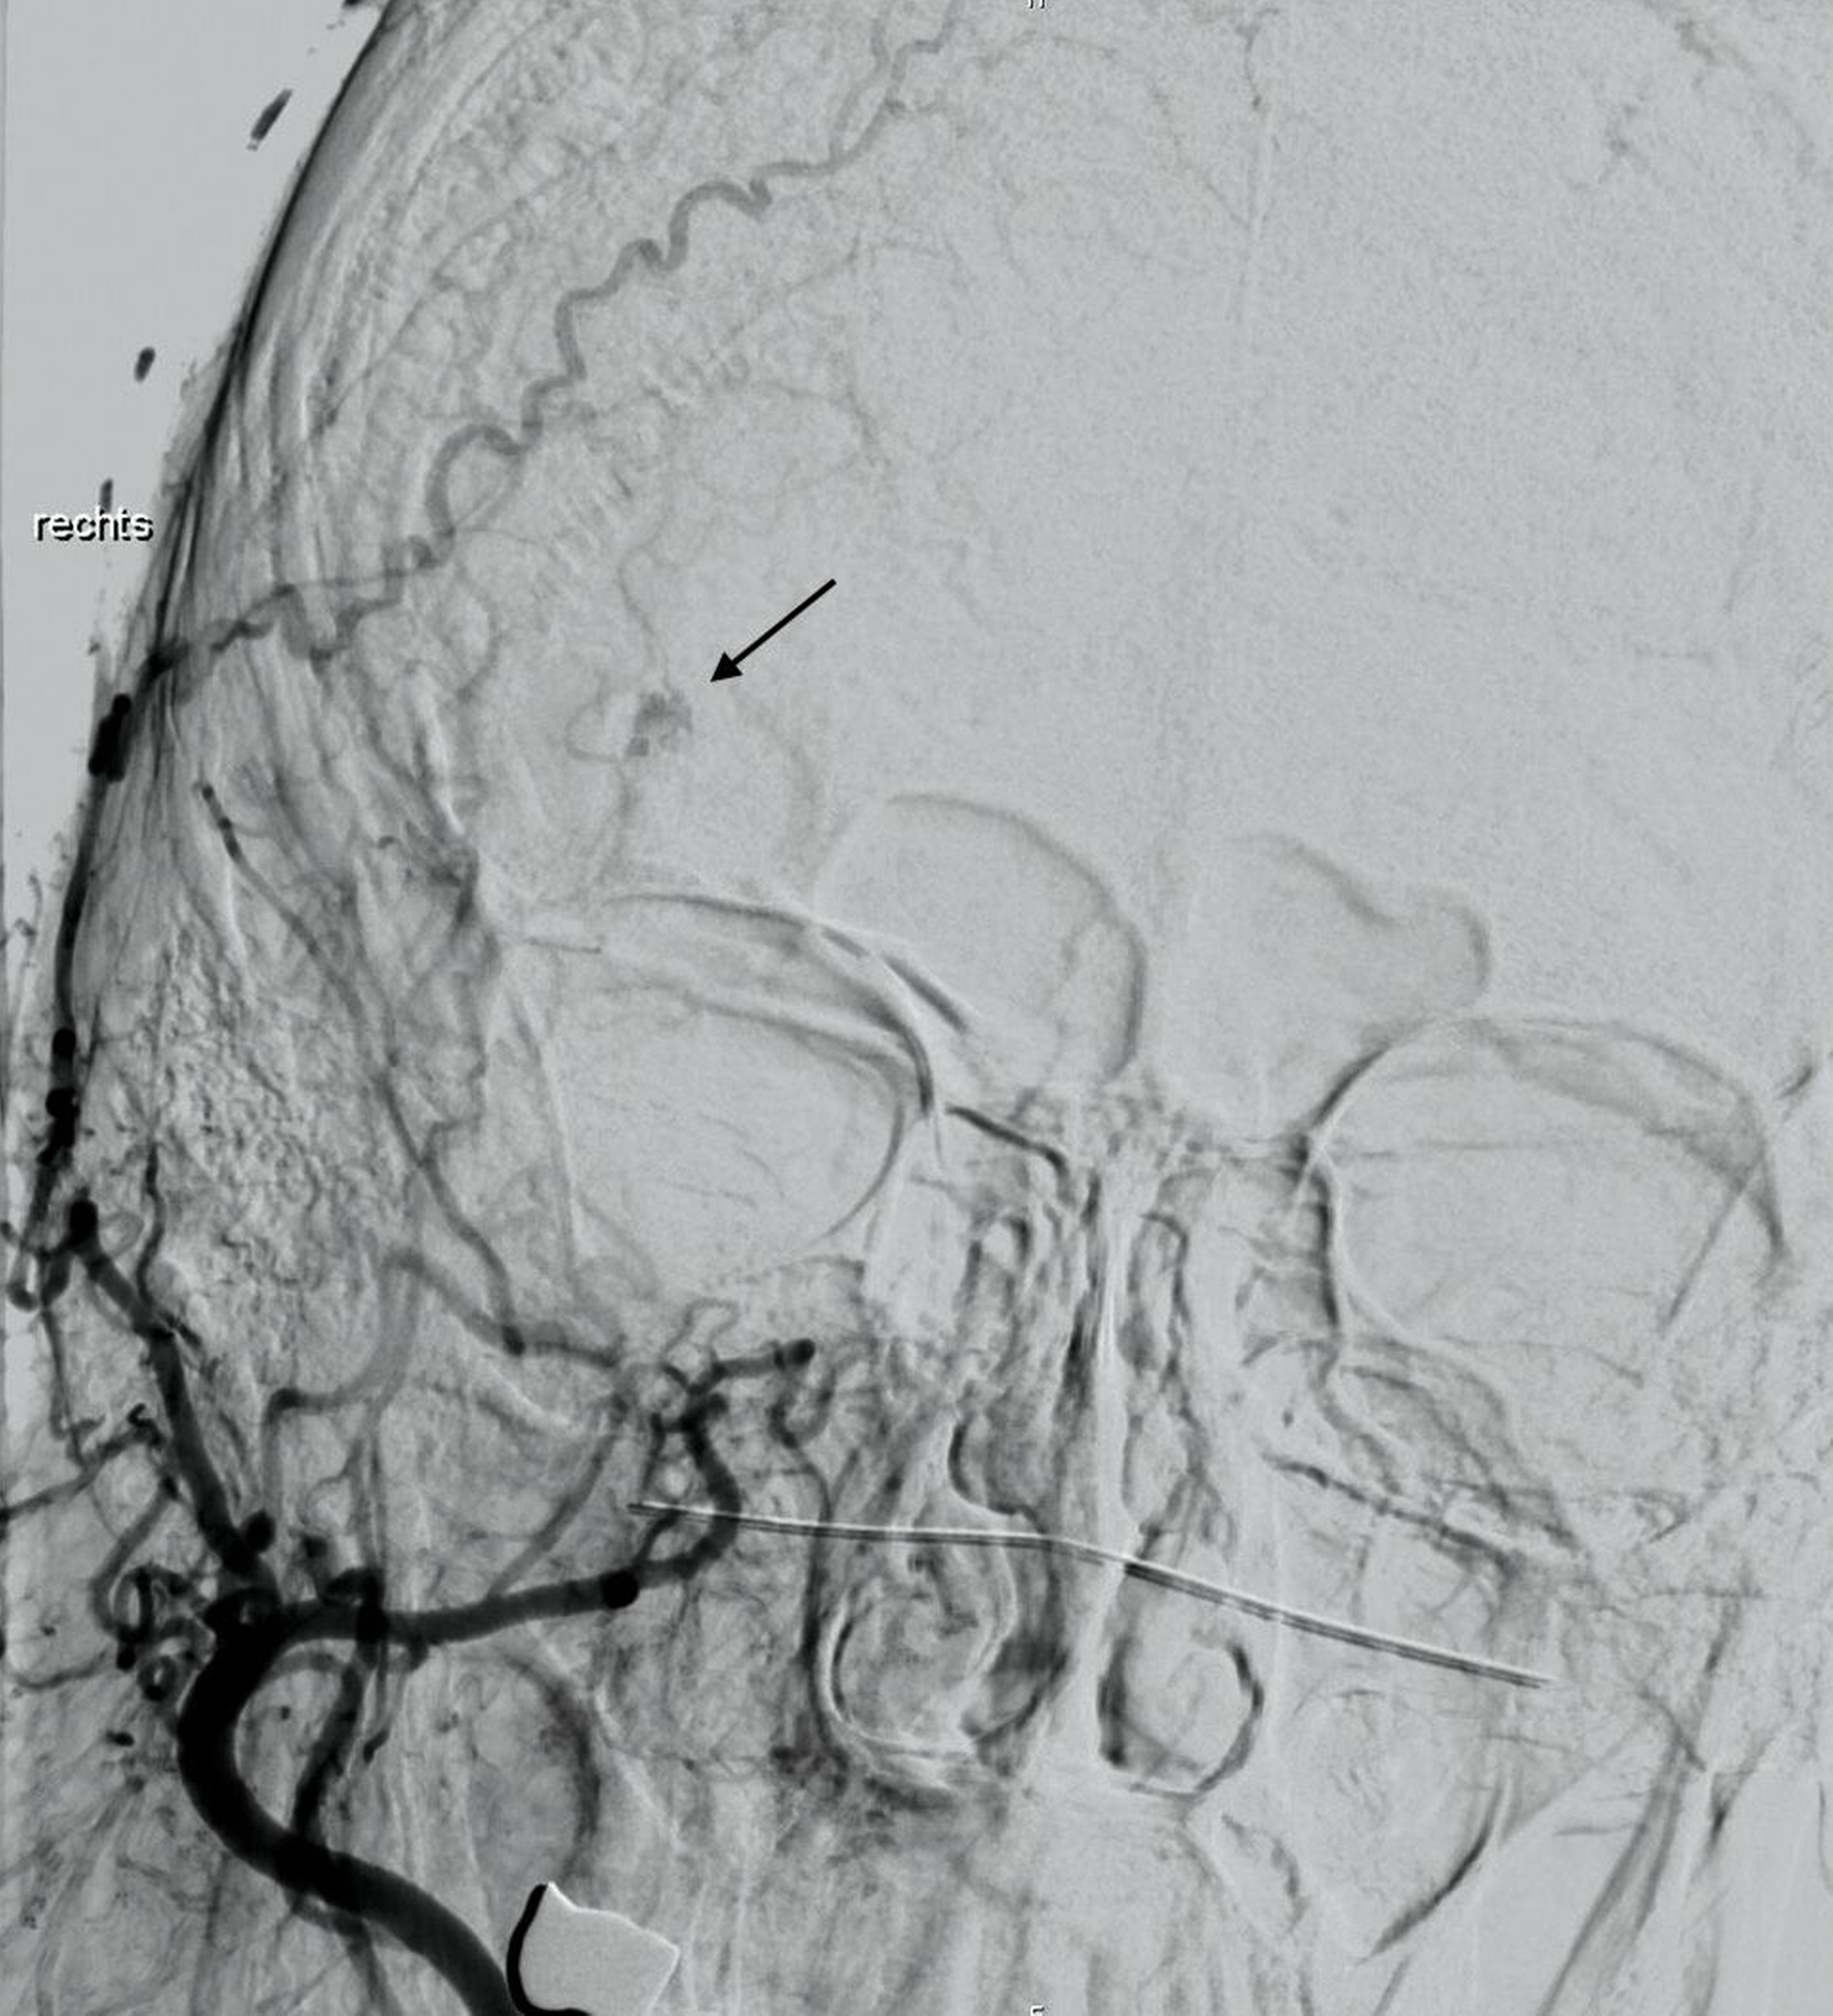

Die anschließend aufgrund der Verdachtsdiagnose durchgeführte Digitale Subtraktionsangiografie (DSA) zeigte einen fokalen Nidus unklarer Entität, der arteriell hauptsächlich über das Stromgebiet der A. carotis externa gespeist wurde (Abbildungen 5 und 6). Nach Vorstellung in einer interdisziplinären Fallkonferenz des Kopf-Hals-Zentrums wurde eine Resektion der Raumforderung über einen bikoronaren Zugang in einer kombiniert mund-, kiefer-, gesichtschirurgisch-neurochirurgischen Operation durchgeführt.

Die knöcherne Defektdeckung erfolgte mit einem Tabula-externa-Transplantat, das vom Os parietale entnommen und mit einer Miniplattenosteosynthese fixiert wurde. Das histomorphologische Bild war am ehesten mit einem kavernösen Hämangiom vereinbar. Die Möglichkeit einer endovaskulären Therapie (zum Beispiel Coiling) war aus radiologischer Sicht nicht gegeben.

Ein weiterer Vorteil einer chirurgischen Entfernung des Befunds ist, dass nur so eine vollständige histopathologische Aufarbeitung und damit die Sicherung der Verdachtsdiagnose erfolgen kann. Ein kombiniert interventionell-chirurgisches Vorgehen mit präoperativem Verschluss eines zuführenden Gefäßes kann bei „high-flow“-Läsionen die perioperative Blutungsgefahr signifikant mindern [Isaac et al., 2018; Konior et al., 1999].